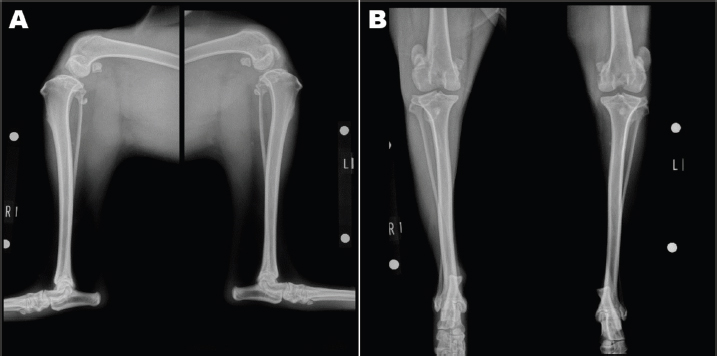

An 11-month-old intact male Siberian Husky was referred to us with the main complication reported as bilateral hind lameness and LPL, diagnosed by a family doctor. His posture showed an X-linked knee. Physiological examination showed bilateral patellar luxation with grade 4 and negative for cranial drawer sign and tibial compression test. The radiograph showed severe bilateral LPL without changes in the hip joint (Figs. 1A-B). His quadriceps (Q) angle showed right=43.37°and left=32.15°. Diazepam 0.1 mg/kg, ketamine 0.5 mg/kg, and fentanyl 5 μg/kg (intravenous), atropine 0.05 mg/kg (intramuscular), and meloxicam 0.2 mg/kg (subcutaneous) were administered as the premedication. After an induction of propofol 6 mg/kg, ropivacaine 0.22 mg/kg was used for epidural anesthesia. Under general anesthesia, the patient was immobilized in the supine position. Surgical techniques included bilateral block trochleoplasty, tibial tuberosity with tension band wiring using Kirschner wire, modified capsules (release of the lateral capsule and suturing of vastus medialis, plication), and the modified MPFL. The modified MPFL was used with the Cruciate Needle (medium, 40 lb) 40# suture (monofilament nylon) single strand (SECUROS, MA), suturing from the lateral aspect of the patella periosteum to the medial sesamoid bone (Figs. 2A-B). The postoperative radiograph is shown in Figures 3A-B. The patient has shown no luxation over 1 year after the operation.

Fig. 3. Postoperative radiograph.